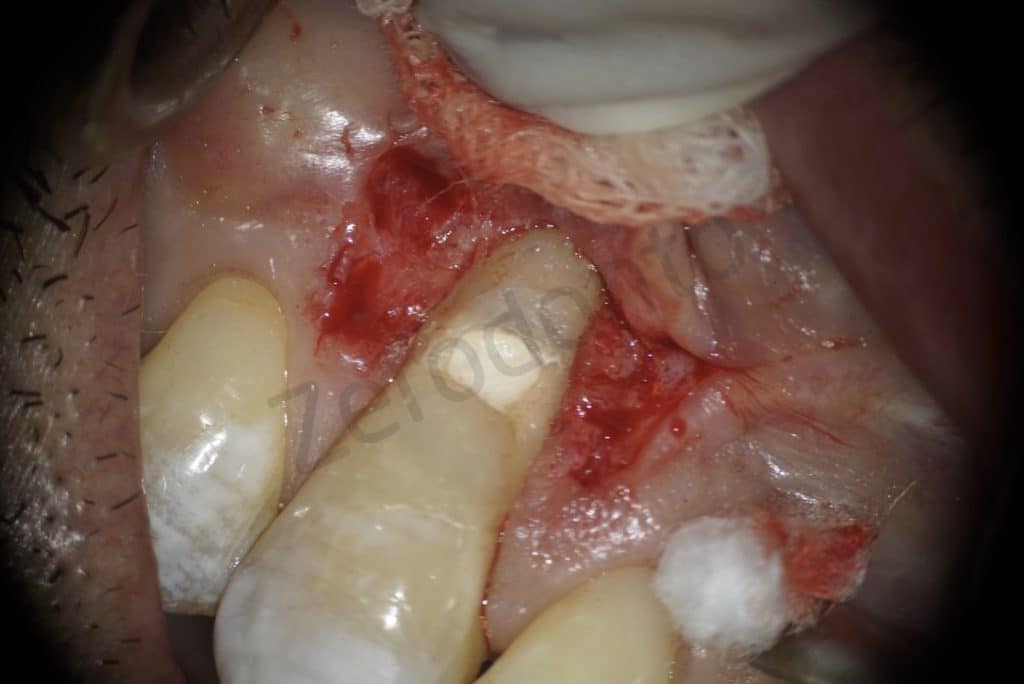

The lesion

Detail of the lesion